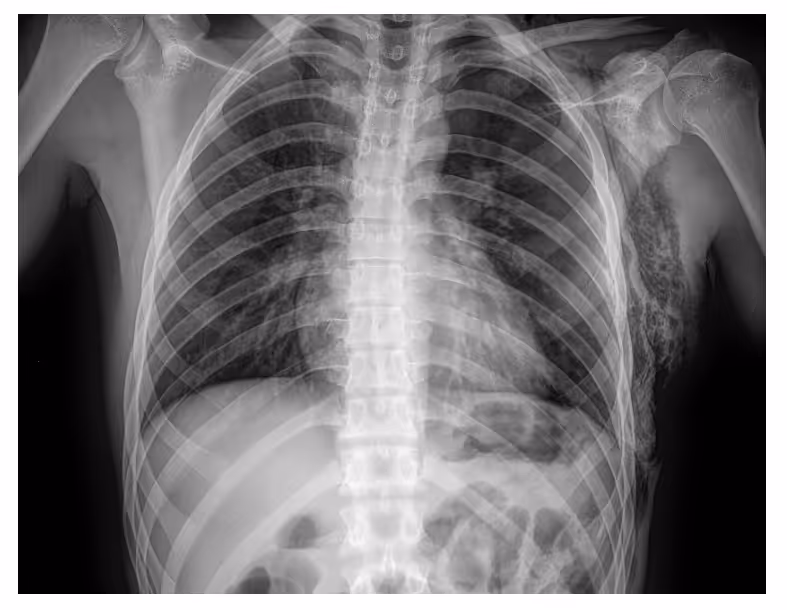

- A 20-year-old male presented with a stab wound to the left hemithorax, and crepitus of the chest was detected upon physical examination.

- Image findings:

- Chest radiograph revealed a left pneumothorax, marked by the visible left pleural edge

- No shift of the mediastinum

- Extensive subcutaneous emphysema over the left chest wall